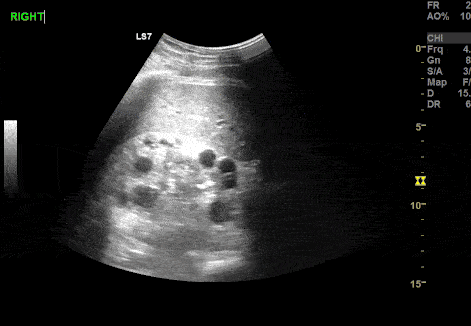

A 12 year old male presented after a MVC. A FAST exam was performed demonstrating incidental finding of Polycystic Kidney Disease (PCKD). Paul Khalil, MD @Khalil3Paul Assistant PEM POCUS director at University of Louisville/Norton Children’s